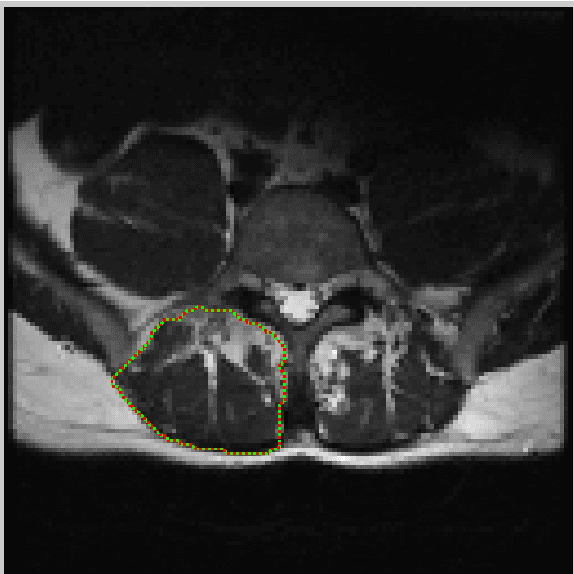

Abstract:In this paper we present an interactive tool that can be used to quantify fat infiltration in lumbar muscles, which is useful in studying fat infiltration and lower back pain (LBP) in adults. Currently, a qualitative assessment by visual grading via a 5-point scale is used to study fat infiltration in lumbar muscles from an axial view of lumbar-spine MR Images. However, a quantitative approach (on a continuous scale of 0-100\%) may provide a greater insight. In this paper, we propose a method to precisely quantify the fat deposition / infiltration in a user-defined region of the lumbar muscles, which may aid better diagnosis and analysis. The key steps are interactively segmenting the region of interest (ROI) from the lumbar muscles using the well known livewire technique, identifying fatty regions in the segmented region based on variable-selection of threshold and softness levels, automatically detecting the center of the spinal column and fragmenting the lumbar muscles into smaller regions with reference to the center of the spinal column, computing key parameters [such as total and region-wise fat content percentage, total-cross sectional area (TCSA) and functional cross-sectional area (FCSA)] and exporting the computations and associated patient information from the MRI, into a database. A standalone application using MATLAB R2014a was developed to perform the required computations along with an intuitive graphical user interface (GUI).